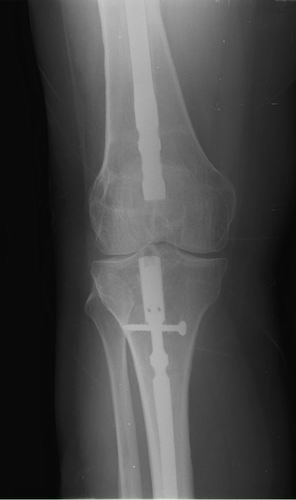

Хочется услышать ваше мнение. Пациентка 48 лет, без вредных привычек,

получила свежую травму (с\3 диафиза правого бедра) при падении с лестницы.

Ранее (8 лет назад) была множественная травма, на бедре–  перелом с\3,

выполнен остеосинтез DFN  Synthes (в др. ЛПУ). Перелом диафиза

консолидировался очень медленно, от реостеосинтеза категорически

отказывалась, в результате к 2 годам наступило сращение. Беспокоили боли

при нагрузке, на рентгенограммах–  зона разрежения вокруг кончика

(проксимального) стержня и проксимальных винтов, согласилась лишь на

удаление дистальных винтов для динамизации стержня. Пациентка пропала из

поля зрения. Затем спустя 2 года при падении получает чрезвертельный

перелом, выполнен остеосинтез бедренным винтом ( DHS ).

Планирую удаление имплантов (кроме проволоки), рассверливание

костно-мозгового канала (сейчас стоит гвоздь 10 мм, попытаюсь

рассверлить до 14-15 диаметра, чтобы поставить 12 мм или 13 мм гвоздь),

внутрикостный остеосинтез блокированным стержнем (динамически).